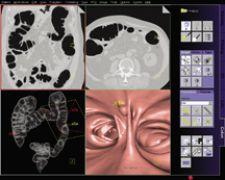

The syngo LungCARE CT application shows a typical CAD mark from syngo Lung CAD.

Where CAD for Colon is Most Effective

The growing adoption of virtual colonoscopy translates into larger data sets for radiologists to read, and clinicians are curious to see if CAD for colon could play an important role as a second reader, particularly when training inexperienced readers.

The Munich Colorectal Cancer Prevention Trial conducted by Anno Graser, M.D., department of Clinical Radiology in Grosshadern (Munich, Germany), evaluated the accuracy of detection with CAD in colonography on patients with same day virtual and optical colonoscopy.

The results showed that Siemens syngo Colonography with PEV routinely detects 90 percent of lesions and polyps in the colon sized 6-25 mm, and according to Dr. Graser, “[t]hose are the most difficult to detect.” They also are the most important — Dr. Graser added, “Size is connected to malignant potential. CAD is inferior when you look at smaller polyps and those that are not clinically significant. A lesion smaller than 5 mm has less than a .01 percent chance of harboring a malignancy.”

Using the results from his study, Dr. Graser believes that a major benefit of CAD is to improve the accuracy of detecting lesions for inexperienced readers. “Experienced readers like myself would be superior to CAD. CAD will operate at 90 percent and inexperienced readers will be around 65 to 70 percent. That improves sensitivity by 20 percent if you use it with inexperienced readers,” he said.

The challenge for CAD continues to be in reducing false positives while maintaining sensitivity. If further honed, this could improve throughput and streamline workflow and potentially even augment the effectiveness of noninvasive procedures. As Dr. Schoepf sees it, “[w]e are moving from computer-aided detection to computer-aided diagnosis. The next step is a new paradigm – to have a computer find something and tell you what it is.”